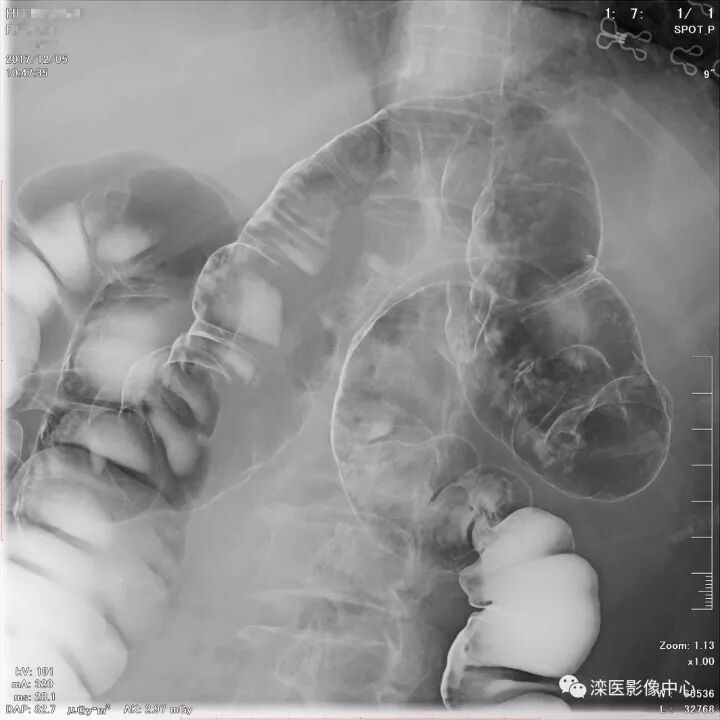

下面请您审阅近期我院影像科开展下消化道双对比造影检查的图像:

(以上图像多角度显示直肠、乙状结肠)